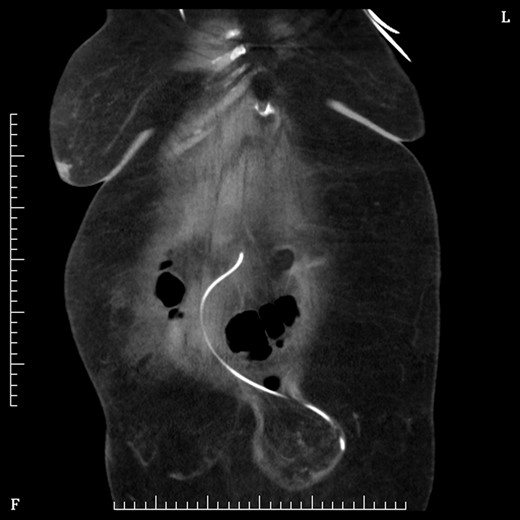

On Day 2 post VP shunt insertion, she was noted to be slow to recover and CT abdomen was performed. This demonstrated that the distal catheter tip was not in the pleural space but entered the abdomen and was redirected out along a tract into an umbilical hernia (Fig. 5). The following day she was taken back to theatre and the VP shunt was revised, and good visualization into the abdomen gave the impression that it was correctly in place. Repeat CT abdomen was performed to confirm placement and to our surprise the catheter had re-entered the same tract and travelled into the umbilical hernia (Fig. 6).

Sagittal figure CT abdomen, demonstrating catheter entering abdomen and re-exiting out the umbilical hernia.